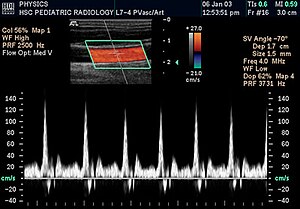

Допплеровский режим (допплерография)

Выделяют несколько допплеровских (позволяющих оценить скорость, направление кровотока) режимов:

- постоянный, отображающий временной график изменения показателей скорости кровотока на протяжении ультразвукового пучка;

- импульсный, при котором врач получает временной график изменения скорости кровотока в заданном контрольном объёме;

- цветовой, когда выполняется одномоментная регистрация кровотока в 64-256 контрольных объёмах с дальнейшей цветовой кодировкой основных параметров;

- энергетический, основанный на принципе цветного допплеровского режима, для повышения чувствительности которого к низкоскоростным потокам присоединяется интеграл мощности спектра допплер-сигнала;

- режим двойной гармоники, основанный на свойстве ультразвука, отраженного от микропузырьков газа (эхоконтраста), удваивать свою частоту по сравнению с исходной.